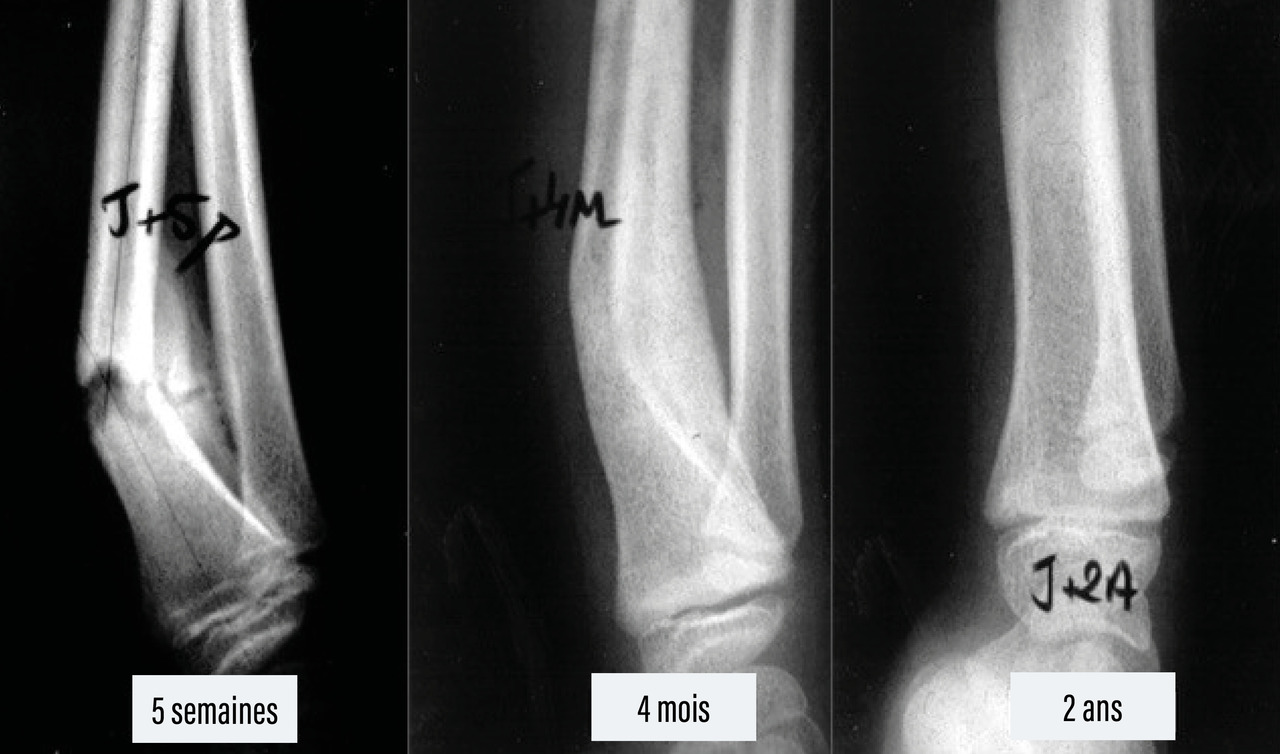

Le cal périphérique produit par le périoste est très volumineux et se constitue rapidement chez l’enfant. Il englobe le foyer de fracture et permet la réalisation plus tardive du cal central, puis du remodelage. Le remodelage du cal se fait par l’apposition d’os par le périoste du côté de la concavité du cal vicieux et par sa résorption du côté de la convexité.

Concernant les fractures à distance du cartilage de croissance, le remodelage du cal et la croissance épiphysaire atténuent, voire corrigent, les éventuels cals vicieux.7

Il y a, par exemple, un fort potentiel de remodelage des fractures du quart inférieur des deux os de l’avant-bras.

Une poussée de croissance post-fracturaire atténue ou corrige les inégalités par chevauchements.